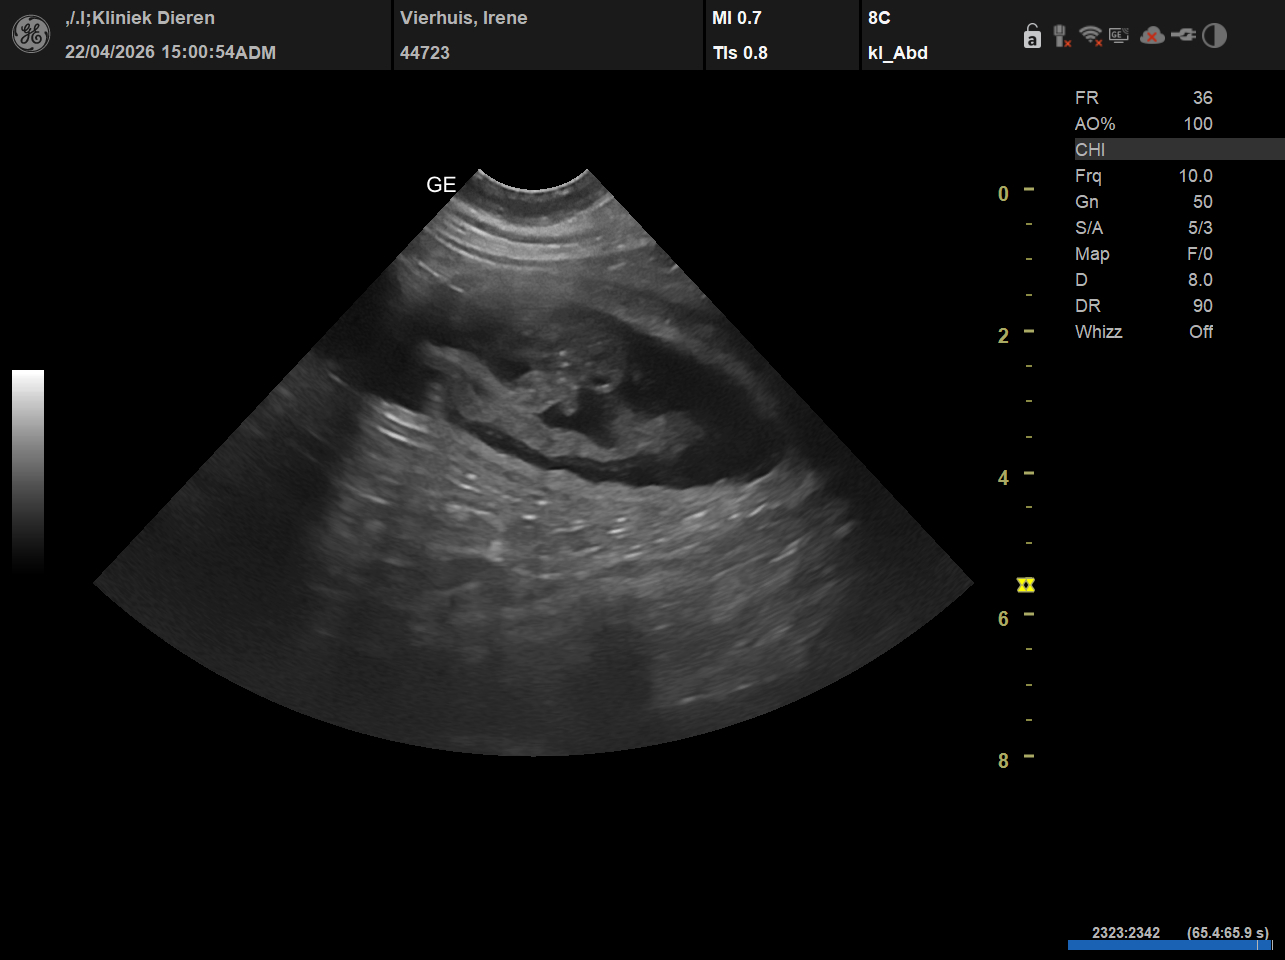

Tijdens de echo heeft de DA rond de tien vruchtjes gezien. Dat moment… dat scherm zien, hartjes zien, weten dat er leven groeit… dat vergeet je niet.